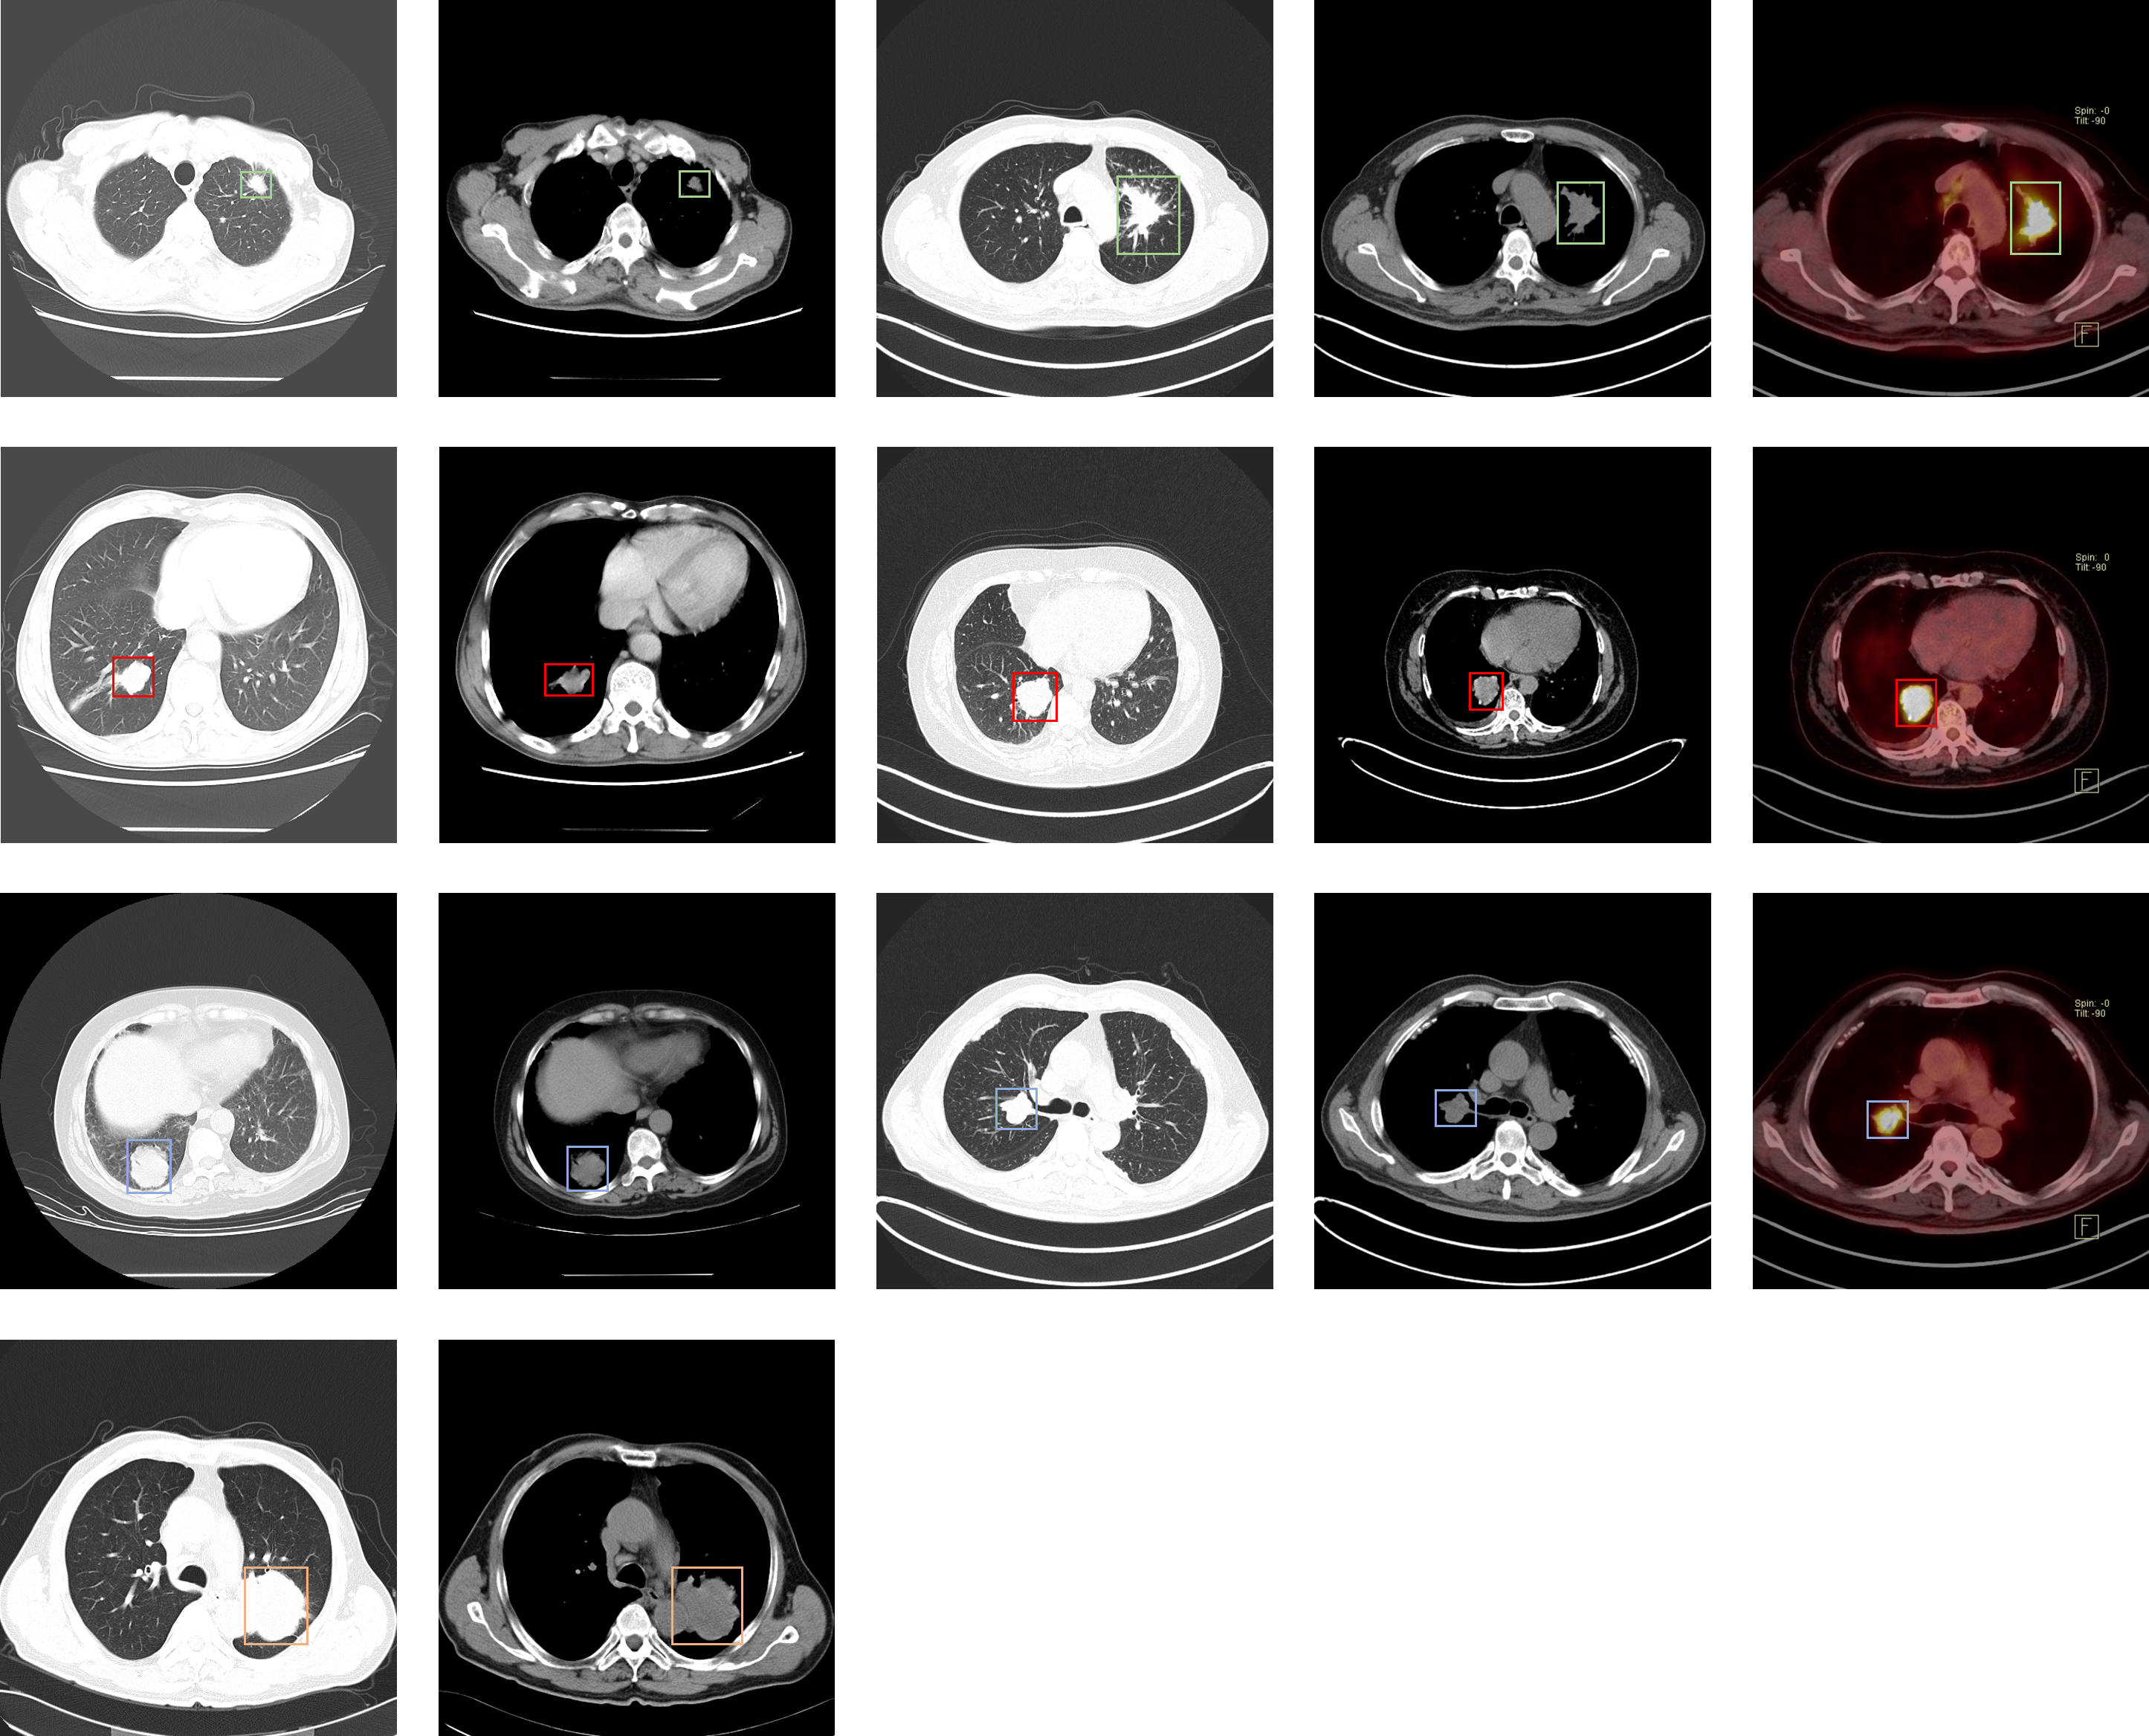

### Lung-PET-CT-Dx

| 名称 | 标注内容 | 类型 | 模态 | 数量 | 标签格式 | 文件格式 |

| - | - | - | - | - | - | - |

| [Lung-PET-CT-Dx](https://wiki.cancerimagingarchive.net/pages/viewpage.action?pageId=70224216) | 肺癌 | 目标检测 | CT | 363 | xml | dcm |